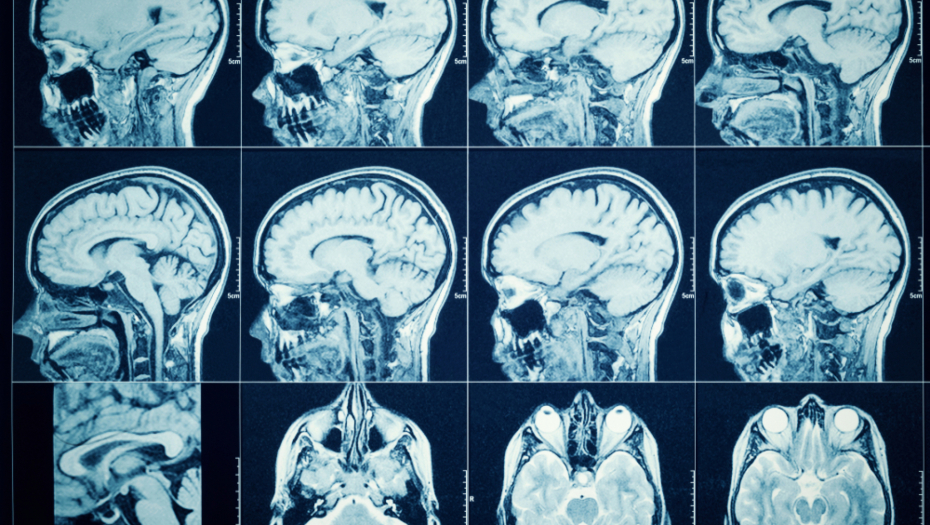

Nakon skeniranja glave, otkrivene su ciste uzrokovane larvama pantljičara, a dodatni testovi su potvrdili infekciju svinjskom pantljičarom.

Ova vrsta parazita obično se prenosi unosom larvi iz svinjskog mesa, što može izazvati ozbiljne zdravstvene probleme, uključujući neurološke komplikacije.